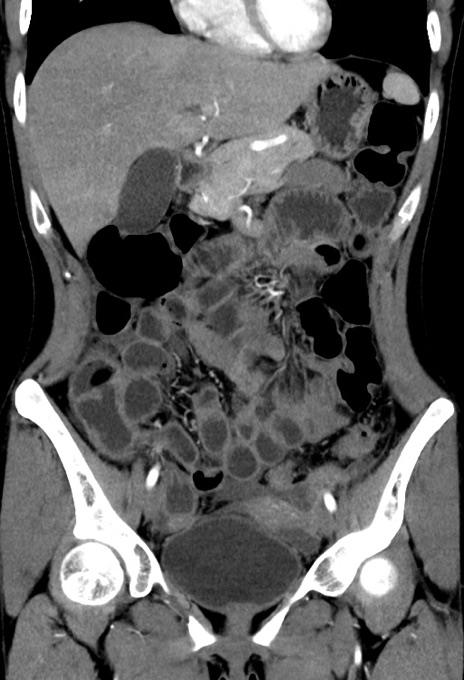

症例17(冠状断像)

【症例】20歳代女性

【主訴】嘔吐、下腹部痛

【現病歴】昨日夕食後に嘔吐し下腹部痛が出現。本日になっても嘔吐持続し改善しないため来院。

【身体所見】意識清明、BT 37.2℃、BP 108/67mmHg、腹部:平坦、やや硬、下腹部正中から右にかけて圧痛あり、反跳痛軽度あり、tapping pain(+)。

【データ】WBC 13600、CRP 14.94